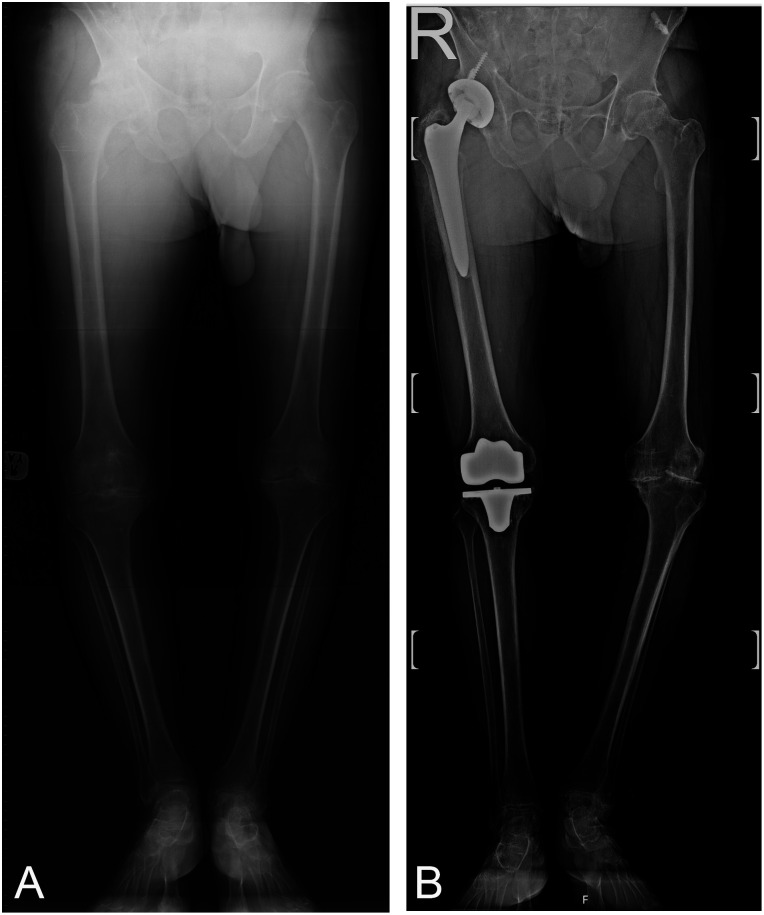

Methods: A retrospective database search identified five patients with severe factor 8 deficiencies who underwent simultaneous hip and knee joint replacement surgery between 2002-2018. Preoperative and postoperative evaluations included Harris Hip Score (HHS), Knee Society Score (KSS), Knee Injury and Osteoarthritis Outcome Score (KOOS), range of motion, flexion contracture (FC), Visual Analog Scale (VAS), hip-knee angle, and leg length discrepancy.

Results: The mean age of the patients was 50.8 years, with a mean follow-up duration of 60 months. Preoperative knee ROM was 55 degrees, improving to 73.8 degrees postoperatively. Preoperative knee FC was 13.7 degrees, improving to 10 degrees postoperatively. HHS increased from 45.6 to 75.7, KSS increased from 36 to 69.3, and KOOS total score increased from 34.4 to 82.7. VAS scores decreased from 6.3 to 1.3. One patient experienced prolonged bleeding and subsequent complications, while the others showed significant improvements.